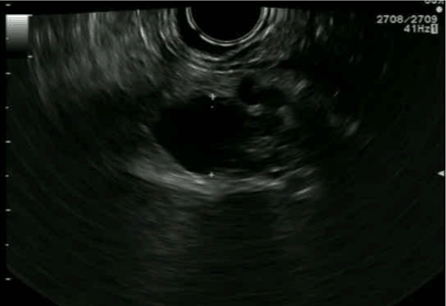

Since a diagnosis of pancreatic mucinous neoplasia could not be ruled out, a decision to perform pancreatic resection was made. Laparoscopic distal pancreatectomy with splenectomy was done. Postoperative course was uneventful and the patient was discharged without complications five days after surgery. The histopathological report revealed hemorrhagic cystic lesion measuring 2 cm, pathological features resembling pancreatic hemangioma without any features of malignancy (Figure 3).

Figure 3: Microscopic examination showing vascular cavities filled with blood surrounded by endothelial cells with fibrous capsule no thrombotic lesions neither features of malignancy.